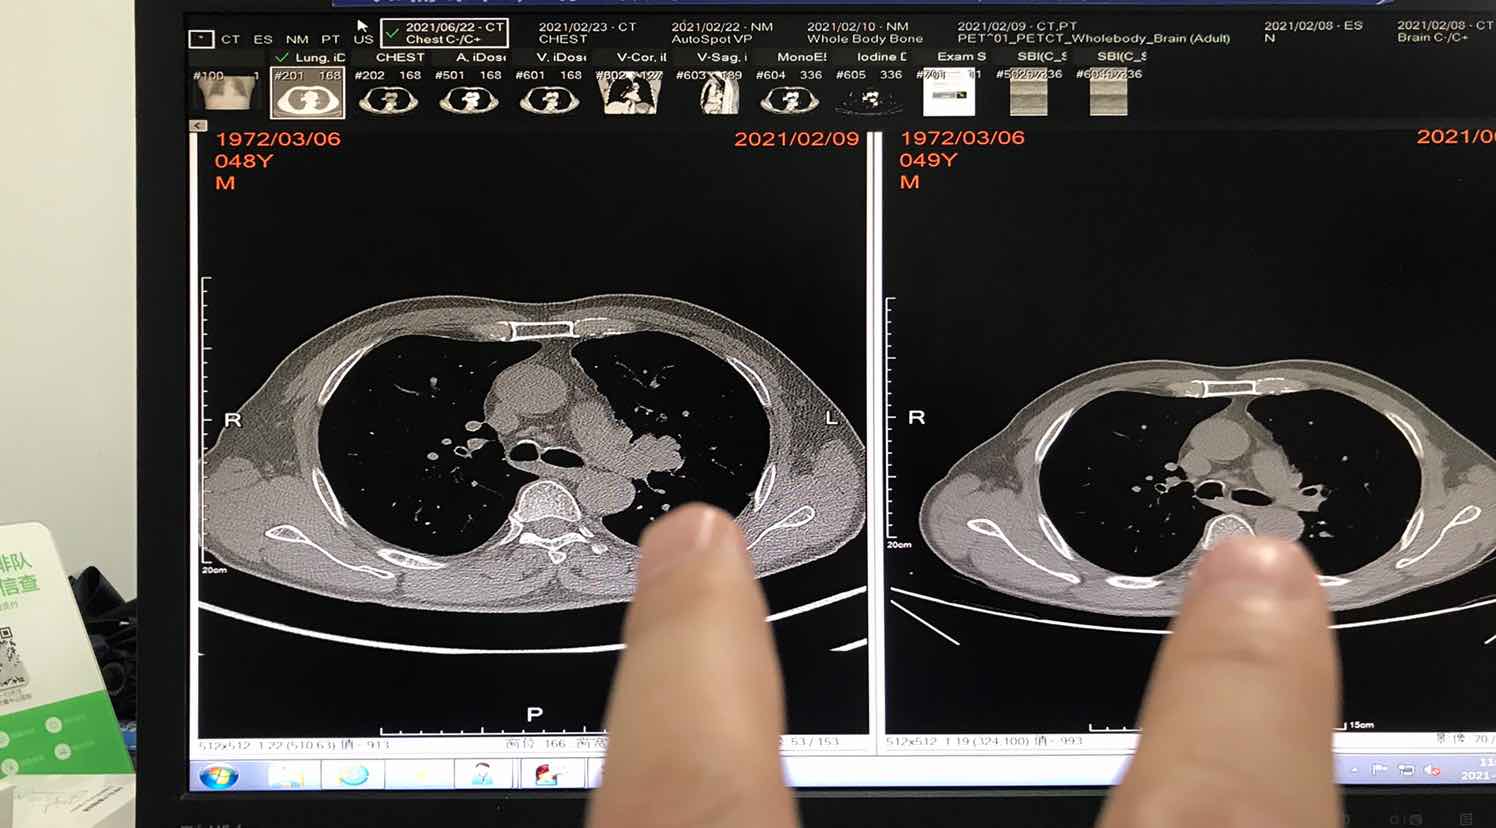

4化结束一个月了,等待华西手术中。迫于好奇心,昨天带我爸去做了个增强CT,今天拿到结果,吃了一惊,报告左肺癌术后,双侧肺门无明显增大,看到这句,我以为拿错报告了,激动的赶紧去找了医生,说看不到病灶了,CR了!下面我大概写一下我父亲的治疗方案。

第三次:同二化,只是在三化前照了CT从最初的2.9*2.8到2.8*2.1再到1.1*0.8,三化后去华西检查,显示肺门少许软组织影,没有测量大小,考虑手术一时半会安排不上,回来继续4化

结合前面化疗效果,心里有点好奇4化效果,所以距离4化结束第五周,等待手术中,去做了增强,影像上说CR了!